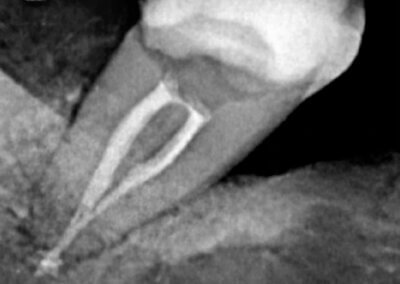

Endodonția este o ramură esențială a stomatologiei, axată pe diagnosticarea, prevenirea și tratamentul afecțiunilor pulpei dentare și a țesuturilor periapicale. Această specialitate joacă un rol crucial în salvarea dinților naturali, evitând extracțiile și menținând sănătatea orală pe termen lung. Prin tehnici avansate și echipamente de ultimă generație, endodonția asigură tratamente precise și eficiente, contribuind la redarea sănătății și funcționalității dinților într-un mod durabil și predictibil.

Utilizarea tehnicilor moderne asigură un tratament rapid, precis și confortabil pentru pacient.

Tratamentele corecte reduc riscul de infecții și complicații viitoare.